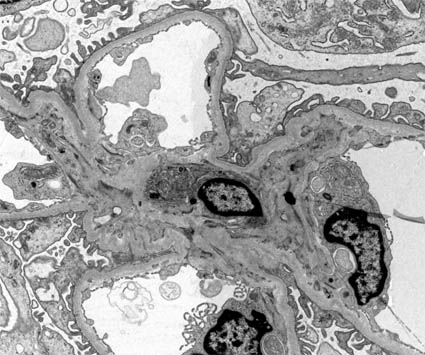

Figura 10. Electron microscopy. Normal glomerulus. In the center a mesangial area in which the nucleus of a mesangial cell (by its location) is recognized, it is surrounded by three capillaries. Note the basement membrane surrounded by podocyte processes. (Original magnification, X2.000).

Figura 10b. Electron microscopy. At higher magnification a capillary light is detailed with some blood material, fenestrated endothelium, basement membrane and podocyte processes. Note that the basement membrane is not present in the portion of the capillary that is in direct contact with the mesangium. (Original magnification, X4.000).